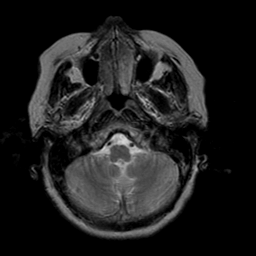

Stroke:T2-weighted MR #2 -- Slice #3

[Home][Help][Clinical] Slice 3